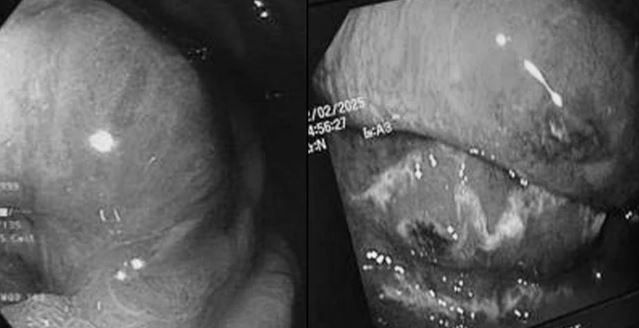

Hình ảnh niêm mạc dạ dày thực quản xung huyết, mủn nát và có lỗ thoát mủ. Ảnh: BVCC.

Kết quả chụp cắt lớp vi tính ổ bụng và nội soi dạ dày thực quản cho thấy phần lớn thành thực quản và dạ dày của người bệnh bị viêm, phù nề kèm theo hoại tử sinh hơi; niêm mạc thực quản - dạ dày xung huyết và mủn nát.